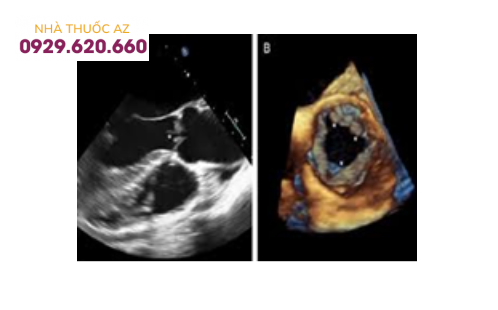

Siêu âm 4D van động mạch chủ (hình đen trắng bên trái là siêu âm 2D với đầu dò qua thực quản)